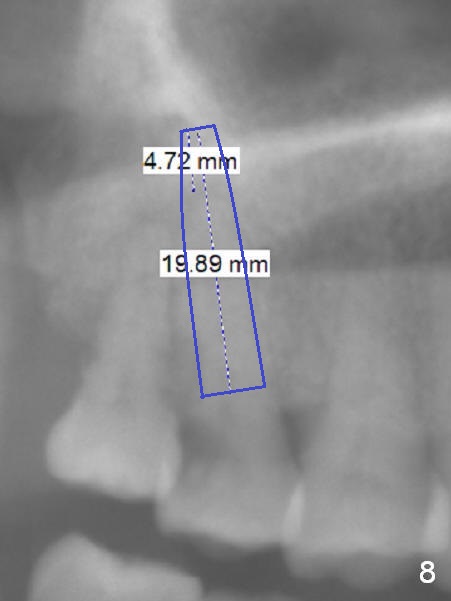

A 52-year-old woman presents to clinic with chief complaint "I can not bite in the upper right". Exam shows DO caries of the tooth #2 (Fig.1). After scaling & root planing and the tooth #1 extraction, pulpotomy is performed at #2. Two months later, pain recurs with swelling. When root canal therapy is finished at #2 (Fig.2-6), the tooth is found to have moderate mobility with guarded to poor prognosis. If the infection does not resolve, extraction and immediate implant seem to be necessary. Considering low bone density around the site of #2, a long implant is indicated (18 mm bone-level, Fig.7,8).